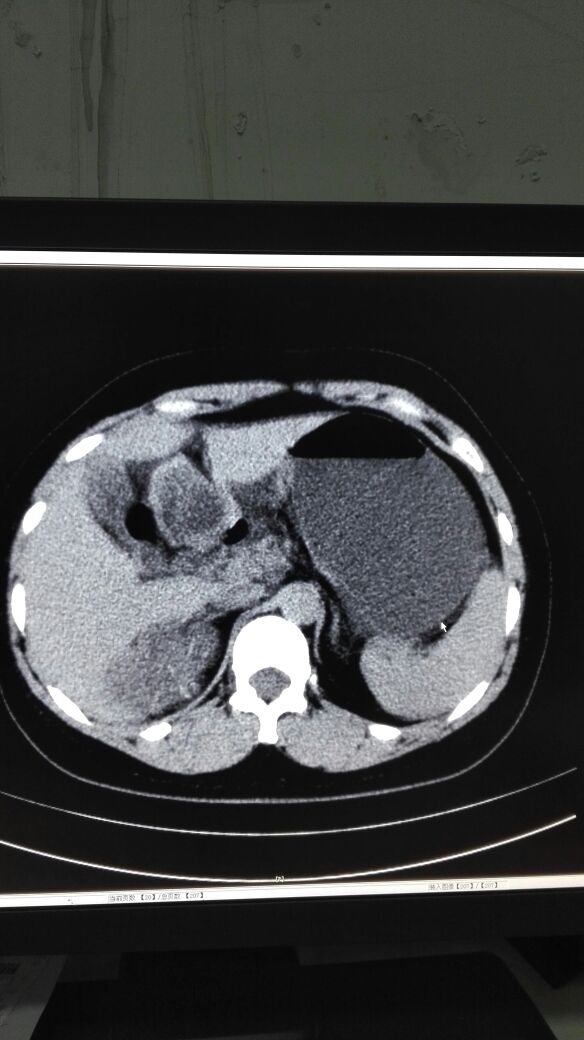

患者女,40岁,医院职工家属。B超体检时发现肝肾间多发囊性占位性病变。行腹部平扫示:右肾上腺区囊性占位,有分割和钙化点,右肾受压下移。诊断意见:右肾上腺囊腺瘤可能性大,建议进一步检查明确。后到市级医院检查并切除手术,病理切片考虑肾上腺囊肿。今腰部不适复查CT片。